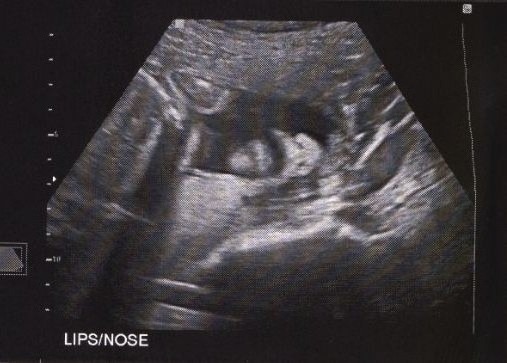

OH – and everything looked normal at my ultrasound today!!! SUCH a relief. I was a little worried that I was heading in the direction of pre-term labor due to some funny feelings down below (see this post for the why) but thankfully things not only looked normal but they were more normal than before. AND the baby was head down!!! I’m so glad to know he is capable of going that direction : )

Check out this photo of his nose and mouth we got when we had an unexpected belly ultrasound! I wasn’t expecting to get to see him OR get any photos! He’s cute!

That is a cool ultrasound photo! You can really see what his nose and lips look like.

Wow that was a really great ultra sound you can see his little face so clearly.

LOL, you labeled it and I STILL can’t make out a face or any kind of baby shape! I’m hopeless.

Turn your head to the right… They are big!

It took me a few minutes to see them too. Then it was plain as day! So cute… Looks like he was sleeping!